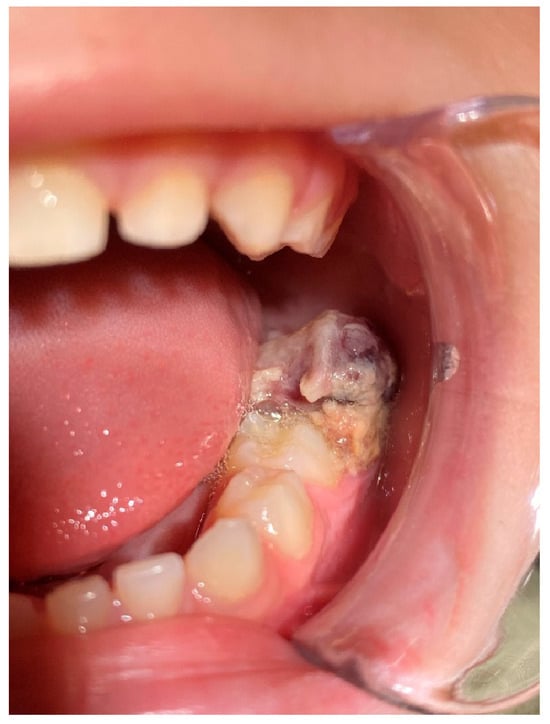

2. Case Presentation